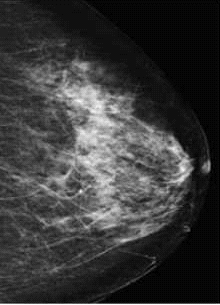

רקמת השד מורכבת מרקמה בלוטית, רקמת חיבור ושומן. בגיל צעיר יש כמות רבה יותר של רקמה בלוטית בשד, ואילו בגיל מבוגר יותר (לאחר גיל המעבר), יש כמות רבה יותר של רקמה שומנית. לעיתים, גם אצל נשים מבוגרות (באחוז מסוים) כמות רקמת השד הפיברוטית-חיבורית רבה יותר מכמות רקמת השומן[1]. ריבוי רקמה פיברוטית ובלוטית יוצר מראה של שד צפוף (ולבן) בממוגרפיה (Mammography), ואילו רקמה שומנית נראית "שקופה" בצילום רנטגן, ושחורה יותר בממוגרפיה. על רקע זה קל יותר לראות הסתיידויות וגידולים, שמתאפיינים במרבית המקרים בצפיפות גבוהה.

צפיפות רקמת שד גבוהה מורידה את רגישות בדיקת הממוגרפיה, שכן רקמת שד צפופה וגושים בשד, נראים בממוגרפיה לבנים. מסיבה זו, כאשר ישנו גוש ברקמת שד צפופה (לבנה), הוא "נבלע" ברקע הלבן ולא ניתן להבדיל ביניהם. במחקר שנערך על ידי מנדלסון ושותפיה[3] הראו החוקרים שכאשר רקמת השד היא בעיקר שומנית, רגישות בדיקת הממוגרפיה עומדת על כ-80%. רגישות זאת צונחת ב-30%, כאשר השד צפוף מאוד.